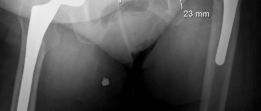

We review everything you need to understand about How We Tackled Massive Bone Loss in a Revision Hip Arthroplasty. A Paprosky IIIB defect signifies severe acetabular massive bone loss, typically seen in revision total hip arthroplasty. It's characterized by >3 cm superior migration of the hip center, significant ischial osteolysis exceeding 15mm, violation of Kohler's line, and obliteration of the teardrop. This complex defect often requires specialized reconstruction due to the extensive bony compromise.

* Type III: Severe bone loss with compromised columns. Type IIIA features superior and lateral migration ("up and out") with an intact teardrop. Type IIIB features medial and superior migration ("up and in") with teardrop obliteration and high risk of pelvic discontinuity.

In the presence of Paprosky IIIB defects or pelvic discontinuity (a complete separation of the superior and inferior hemipelvis), the reconstructive complexity escalates significantly. The goal is to bridge the discontinuity and achieve stable fixation in both the ilium and the ischium/pubis.